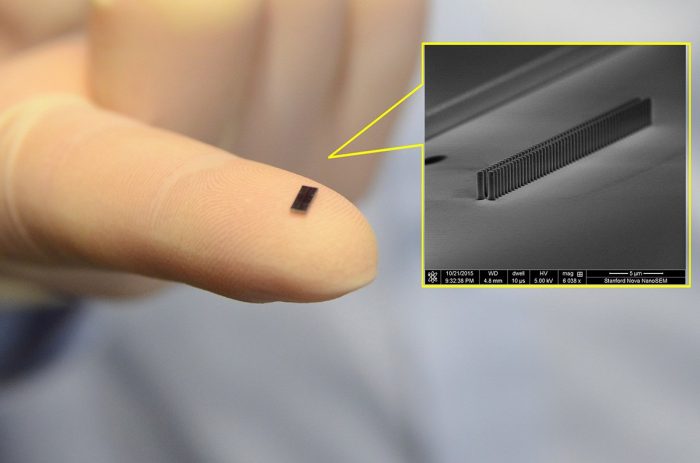

A Stanford Egyetem kutatói létrehoztak egy vákuumba zárt szilícium chipet, amely képes elektronok gyorsítására infravörös lézer használatával. A kicsiny részecskegyorsítót a jövőben olyan kémiai, biológiai és orvosi célú kísérletekhez használhatják, amelyekhez nincs szükség az óriás részecskegyorsítók energiájára.

A Science című tudományos folyóiratban közzétett tanulmányukban mutatták be új fejlesztésüket az egyetemen lévő nemzeti részecskegyorsító laboratórium (SLAC) kutatói.

“A legnagyobb részecskegyorsítók olyanok, mint az óriás teleszkópok. Nagyon kevés létezik a világon, és a kutatóknak el kell utazniuk azokra a helyekre, ahol ezek működnek” – mondta Jelena Vuckovic, a kutatócsoport vezetője.

“Miniatürizálni akarjuk a részecskegyorsító technológiát oly módon, hogy az széles körben hozzáférhető legyen mint kutatási eszköz” – tette hozzá.

Fotó: phys.org

A kutatók azt tervezik, hogy 2020 végére az alig hüvelyknyi (2,5 centiméter) chipen a fénysebesség 94 százalékán – vagy egymillió elektronvolton – lesznek képesek elektront gyorsítani.

A chipre épített részecskegyorsító technológiája elvezethet új radiológiai terápiákhoz a daganatos betegségek kezelésében. Jelenleg a röntgengépek egy szobát elfoglalnak, és a betegeknek védőpajzsot kell viselniük a járulékos károsodás elkerülésére.

“Tanulmányunkban elkezdtük bemutatni, hogy lehet elektron sugárnyalábot közvetlenül a tumorba juttatni úgy, hogy az egészséges szöveteket nem károsítjuk” – mondta Robert Byer, a tanulmány társszerzője.